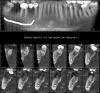

dent-a Опубликовано 1 июля, 2011 Поделиться Опубликовано 1 июля, 2011 Уважаемые, кому не лень - посоветуйте как .... ммм правильнее поступить в данном клиническом случае:? поставить пятёрочку (5.0) и будет благодать или есть всё же смысл установить два имплантата меньшего диаметра (3.75 + 3.75 или 3.75 + 4.2) учитывая, что ширина хорошая. (возможно и не в конкретном случае а вообще при аналогичных ситуациях). Спасибо большое за ответы. на всякий случай - дубль ссылкиzooo.jpeg Ссылка на комментарий

doca Опубликовано 1 июля, 2011 Поделиться Опубликовано 1 июля, 2011 Уважаемые, кому не лень - посоветуйте как .... ммм правильнее поступить в данном клиническом случае:? поставить пятёрочку (5.0) и будет благодать или есть всё же смысл установить два имплантата меньшего диаметра (3.75 + 3.75 или 3.75 + 4.2) учитывая, что ширина хорошая. (возможно и не в конкретном случае а вообще при аналогичных ситуациях). Спасибо большое за ответы. на всякий случай - дубль ссылкиzooo.jpegПосмотрите чуть шире,46.48 уходят,44тоже нужно смотреть,так что минимум 2 импланта Ссылка на комментарий

dent-a Опубликовано 1 июля, 2011 Автор Поделиться Опубликовано 1 июля, 2011 Посмотрите чуть шире,46.48 уходят,44тоже нужно смотреть,так что минимум 2 импланта Тоже верно, но пока что речь только про 4.7 ) спасибо) Ссылка на комментарий

doca Опубликовано 1 июля, 2011 Поделиться Опубликовано 1 июля, 2011 Тоже верно, но пока что речь только про 4.7 ) спасибо)это в принципе неправильно,потом может аукнуться,но если конкретно этот участок то только один имплант,хоть четверка в диаметре и можно не парится. Ссылка на комментарий

Bier Опубликовано 2 июля, 2011 Поделиться Опубликовано 2 июля, 2011 только 1 имплантат в эту зону. Ссылка на комментарий